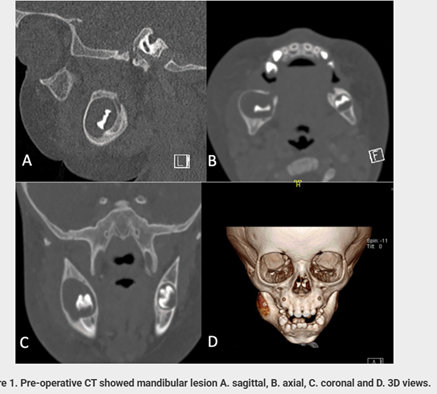

- CT imaging revealed:

- A well-defined, expansile radiolucent lesion

- Located in the posterior mandible

- Associated with an unerupted tooth

- Approximate size: 1.6 × 1.3 cm

The radiographic appearance strongly suggested a dentigerous cyst, with inflammatory pathology considered as a differential diagnosis.